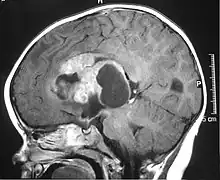

| MRI of an AT/RT | |

- Magnetic resonance imaging (MRI) of the brain and spine

The initial diagnosis of a tumor is made with a radiographic study (MRI[22] or CT-). If CT was performed first, an MRI is usually performed as the images are often more detailed and may reveal previously undetected metastatic tumors in other locations of the brain. In addition, an MRI of the spine is usually performed. The AT/RT tumor often spreads to the spine. AT/RT is difficult to diagnose only from radiographic study; usually, a pathologist must perform a cytological or genetic analysis.

Appearance on radiologic exam

AT/RTs can occur at any sites within the CNS; however, about 60% are located in the posterior fossa or cerebellar area. The ASCO study showed 52% posterior fossa; 39% sPNET; 5% pineal; 2% spinal, and 2% multifocal.[3]

The tumors' appearance on CT and MRI are not specific, tending towards large size, calcifications, necrosis (tissue death), and hemorrhage (bleeding). Radiological studies alone cannot identify AT/RT; a pathologist almost always has to evaluate a brain tissue sample.

The increased cellularity of the tumor may make the appearance on an uncontrasted CT to have increased attenuation. Solid parts of the tumor often enhance with contrast MRI finding on T1 and T2 weighted images are variable. Precontrast T2 weighted images may show an isosignal or slightly hypersignal. Solid components of the tumor may enhance with contrast, but not always. MRI studies appear to be more able to pick up metastatic foci in other intracranial locations, as well as intraspinal locations.

Preoperative and follow-up studies are needed to detect metastatic disease.